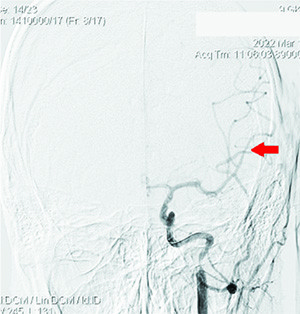

Рисунок 2. Окклюзия ВСА слева, коллатеральное заполнение сосудов левой гемисферы из правой ВСА и позвоночных артерий.Спустя 40 минут после начала тромболизисной терапии пациентка доставлена в ангиографический кабинет для проведения рентгенэндоваскулярного вмешательства.

Проведена диагностика: определялась окклюзия несколько дистальнее устья ВСА слева, коллатеральное заполнение сосудов левой гемисферы из правой ВСА и позвоночных артерий, локальная окклюзия ветвей первого порядка левой СМА после бифуркации (см. рис. 2 и 3).